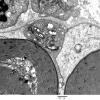

PERIPHERAL NEUROPATHY

7B CIDP (3)